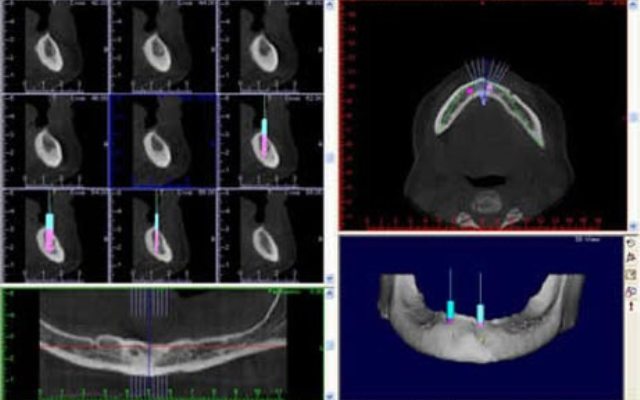

Reformatação computadorizada com DentalSlice

Para trabalhar no DentalSlice basta solicitar na Clinica Serraro a tomografia computadorizada, onde as imagens DICOM (arquivos da tomografia) serão convertidas para o ambiente DentalSlice criando um arquivo que será enviado para o cirurgião dentista.

O Dental Slice é uma ferramenta de planejamento implantodôntico pré-operatório, desenhado para oferecer auxílio cirúrgico-protético com alto nível de precisão e aumentar a margem de segurança no tratamento.

O programa foi projetado para rodar em computadores pessoais e ambiente Windows.

O programa é acessível a qualquer cirurgião dentista e permite que o planejamento seja realizado pela própria equipe que vai realizar a cirurgia. As imagens também podem ser segmentadas, oferecendo melhor visualização de detalhes, como por exemplo do seio maxilar, canal da mandíbula ou de lesões.